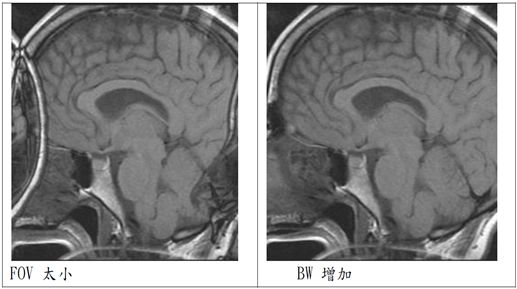

反摺假影(Aliasing artifact):

又稱wrap-around artifact

原理:對一個固定的FOV及梯度強度而言,最大頻率 fmax相對應於FOV的邊緣。一旦FOV外面部分感受到約2倍高的頻率,此較高頻率的FOV會包摺到較低頻率的FOV,而造成 aliasing artifacts。

簡單說就是FOV太小,主要發生在相位編碼方向(phase encoding)。